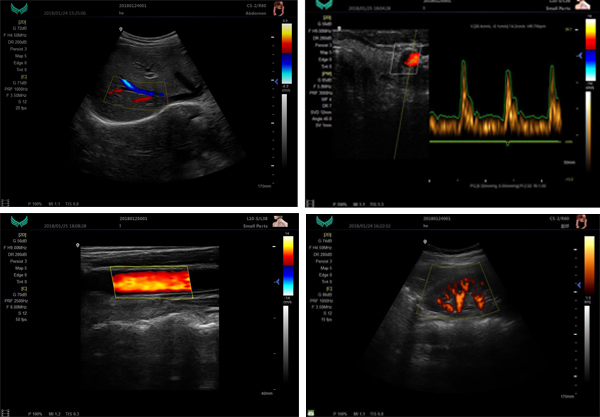

| Product Name: | Color Doppler Ultrasound standing XF7800 |

| Display mode: | B,B/B,M,B/M,CFM,CMF/B,PDI,B/PW, total eight mode |

| Application mode: | abdomen, gynecology, obstetrics, superficial organ, urologist, heart and user defined model 1-4, total ten models |

Xianfeng 7 Series Color Doppler system has a unique shape of elegant atmosphere and the latest generation of application digital color Doppler diagnostic system which can be widely applicable to diagnose abdomen,obstetrics,gynecology,cardiac,mammary gland,musculoskeletal and peripheral vessel.

*B/2B/4B/M/CFM/PDI/PW

*THI(Tissue Harmonic Imaging)

*Real-time 2D and Doppler Double Synchronization.

*Real-time 2D ,Doppler and Color triple synchronization.